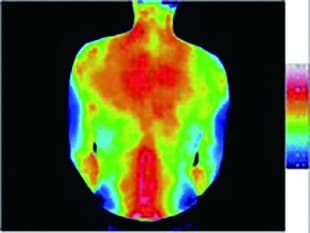

Recoverypro Lab. サーモグラフィー測定結果

Recoverypro Lab.あったか起毛フリース着用

着用直後

30分後

Recoverypro Lab.着用30分後のサーモグラフィ結果がこちら。肌に触れる面が増えるほど効果が高まるため、疲労回復をしっかり実感したい方は上下セットの着用がおすすめです。

体から放出された遠赤外線エネルギーを吸収し、体へと輻射することで血行を促進します